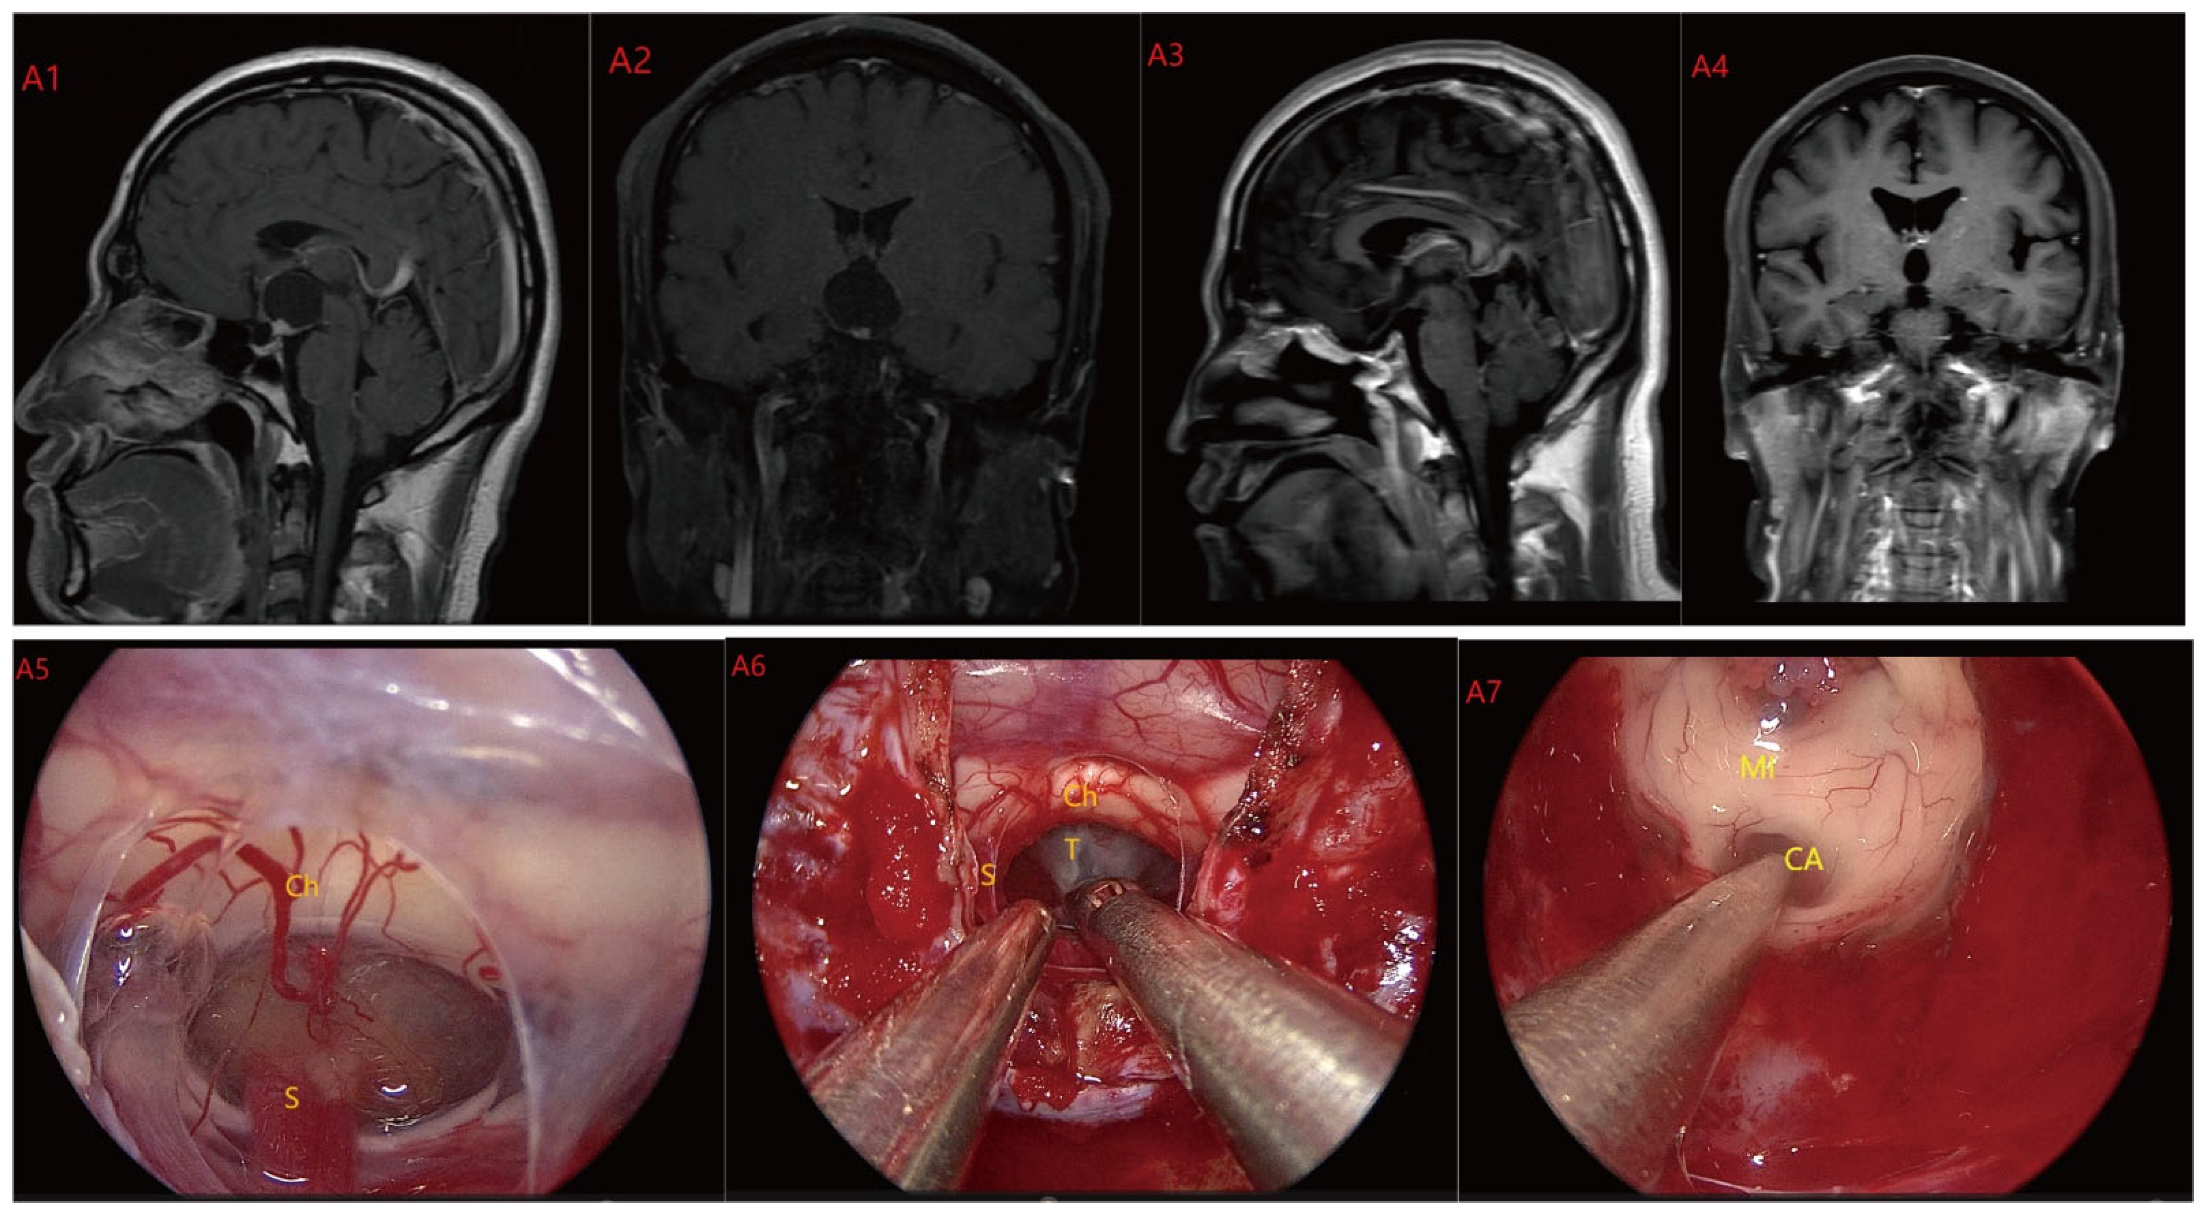

Figure 4.

Case 4 Type III: the tumor grows strictly inside the third ventricle. (A1,A2) The TLTA was used; the pituitary stalk could not be seen during the surgery (A5–A7). Finally, the tumor was totally resected (A3,A4). Optic chiasm (Ch), foramen of Monroe (MF), massa intermedia (MI), cerebral aqueduct (CA), tumor (T).

Figure 5.

Case 5 Type III: the tumor grows strictly inside the third ventricle. (B1,B2) The TCPCA AND TLTA was used; the pituitary stalk could not be seen during the surgery (B5–B7). The TVF was intact. The tumor was finally totally resection (B3,B4). Optic chiasm (Ch), foramen of Monroe (MF), massa intermedia (MI), cerebral aqueduct (CA), tumor (T).